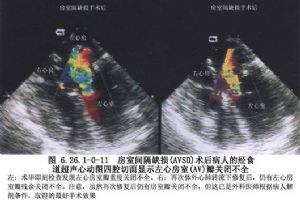

15.5 5.室間隔缺損修復後再通

由於縫線撕脫多發生於術後1~3d。主要原因是手術修復時縫合過淺,三尖瓣隔瓣基底部瓣膜組織薄,結紮縫線時未紮緊,結紮線撕脫等。臨牀檢查可發現心前區收縮期雜音再度出現,甚至有收縮期震顫。病人常有呼吸困難,嚴重者可出現心力衰竭。超聲心動圖檢查可確定診斷。

撕裂口較小,病人無症狀,可暫不手術,密切觀察,有時可自行閉合。否則應再次手術修復。

對晚期殘餘缺損病人,術前應調整病人全身狀態,應用強心、利尿藥物治療,必要時加用擴血管藥物,改善病人心臟功能。晚期殘餘缺損由於心包粘連和心臟與胸骨後粘連。手術時應特別小心分離胸骨後粘連,應用搖擺鋸劈開胸骨或分段鋸開胸骨。如心包與心臟粘連分離困難時,儘早建立體外循環,在轉流及心臟低負荷情況下分離粘連。殘餘缺損多位於三尖瓣隔瓣基底部及缺損後上緣,原補片若已爲心內膜纖維組織覆蓋,無須拆除。根據殘餘缺損大小,另外剪裁補片修復。殘餘缺損修補均用間斷帶墊片褥式縫合,危險區仍縫於三尖瓣隔瓣根部及竇部室間隔之右心室面。